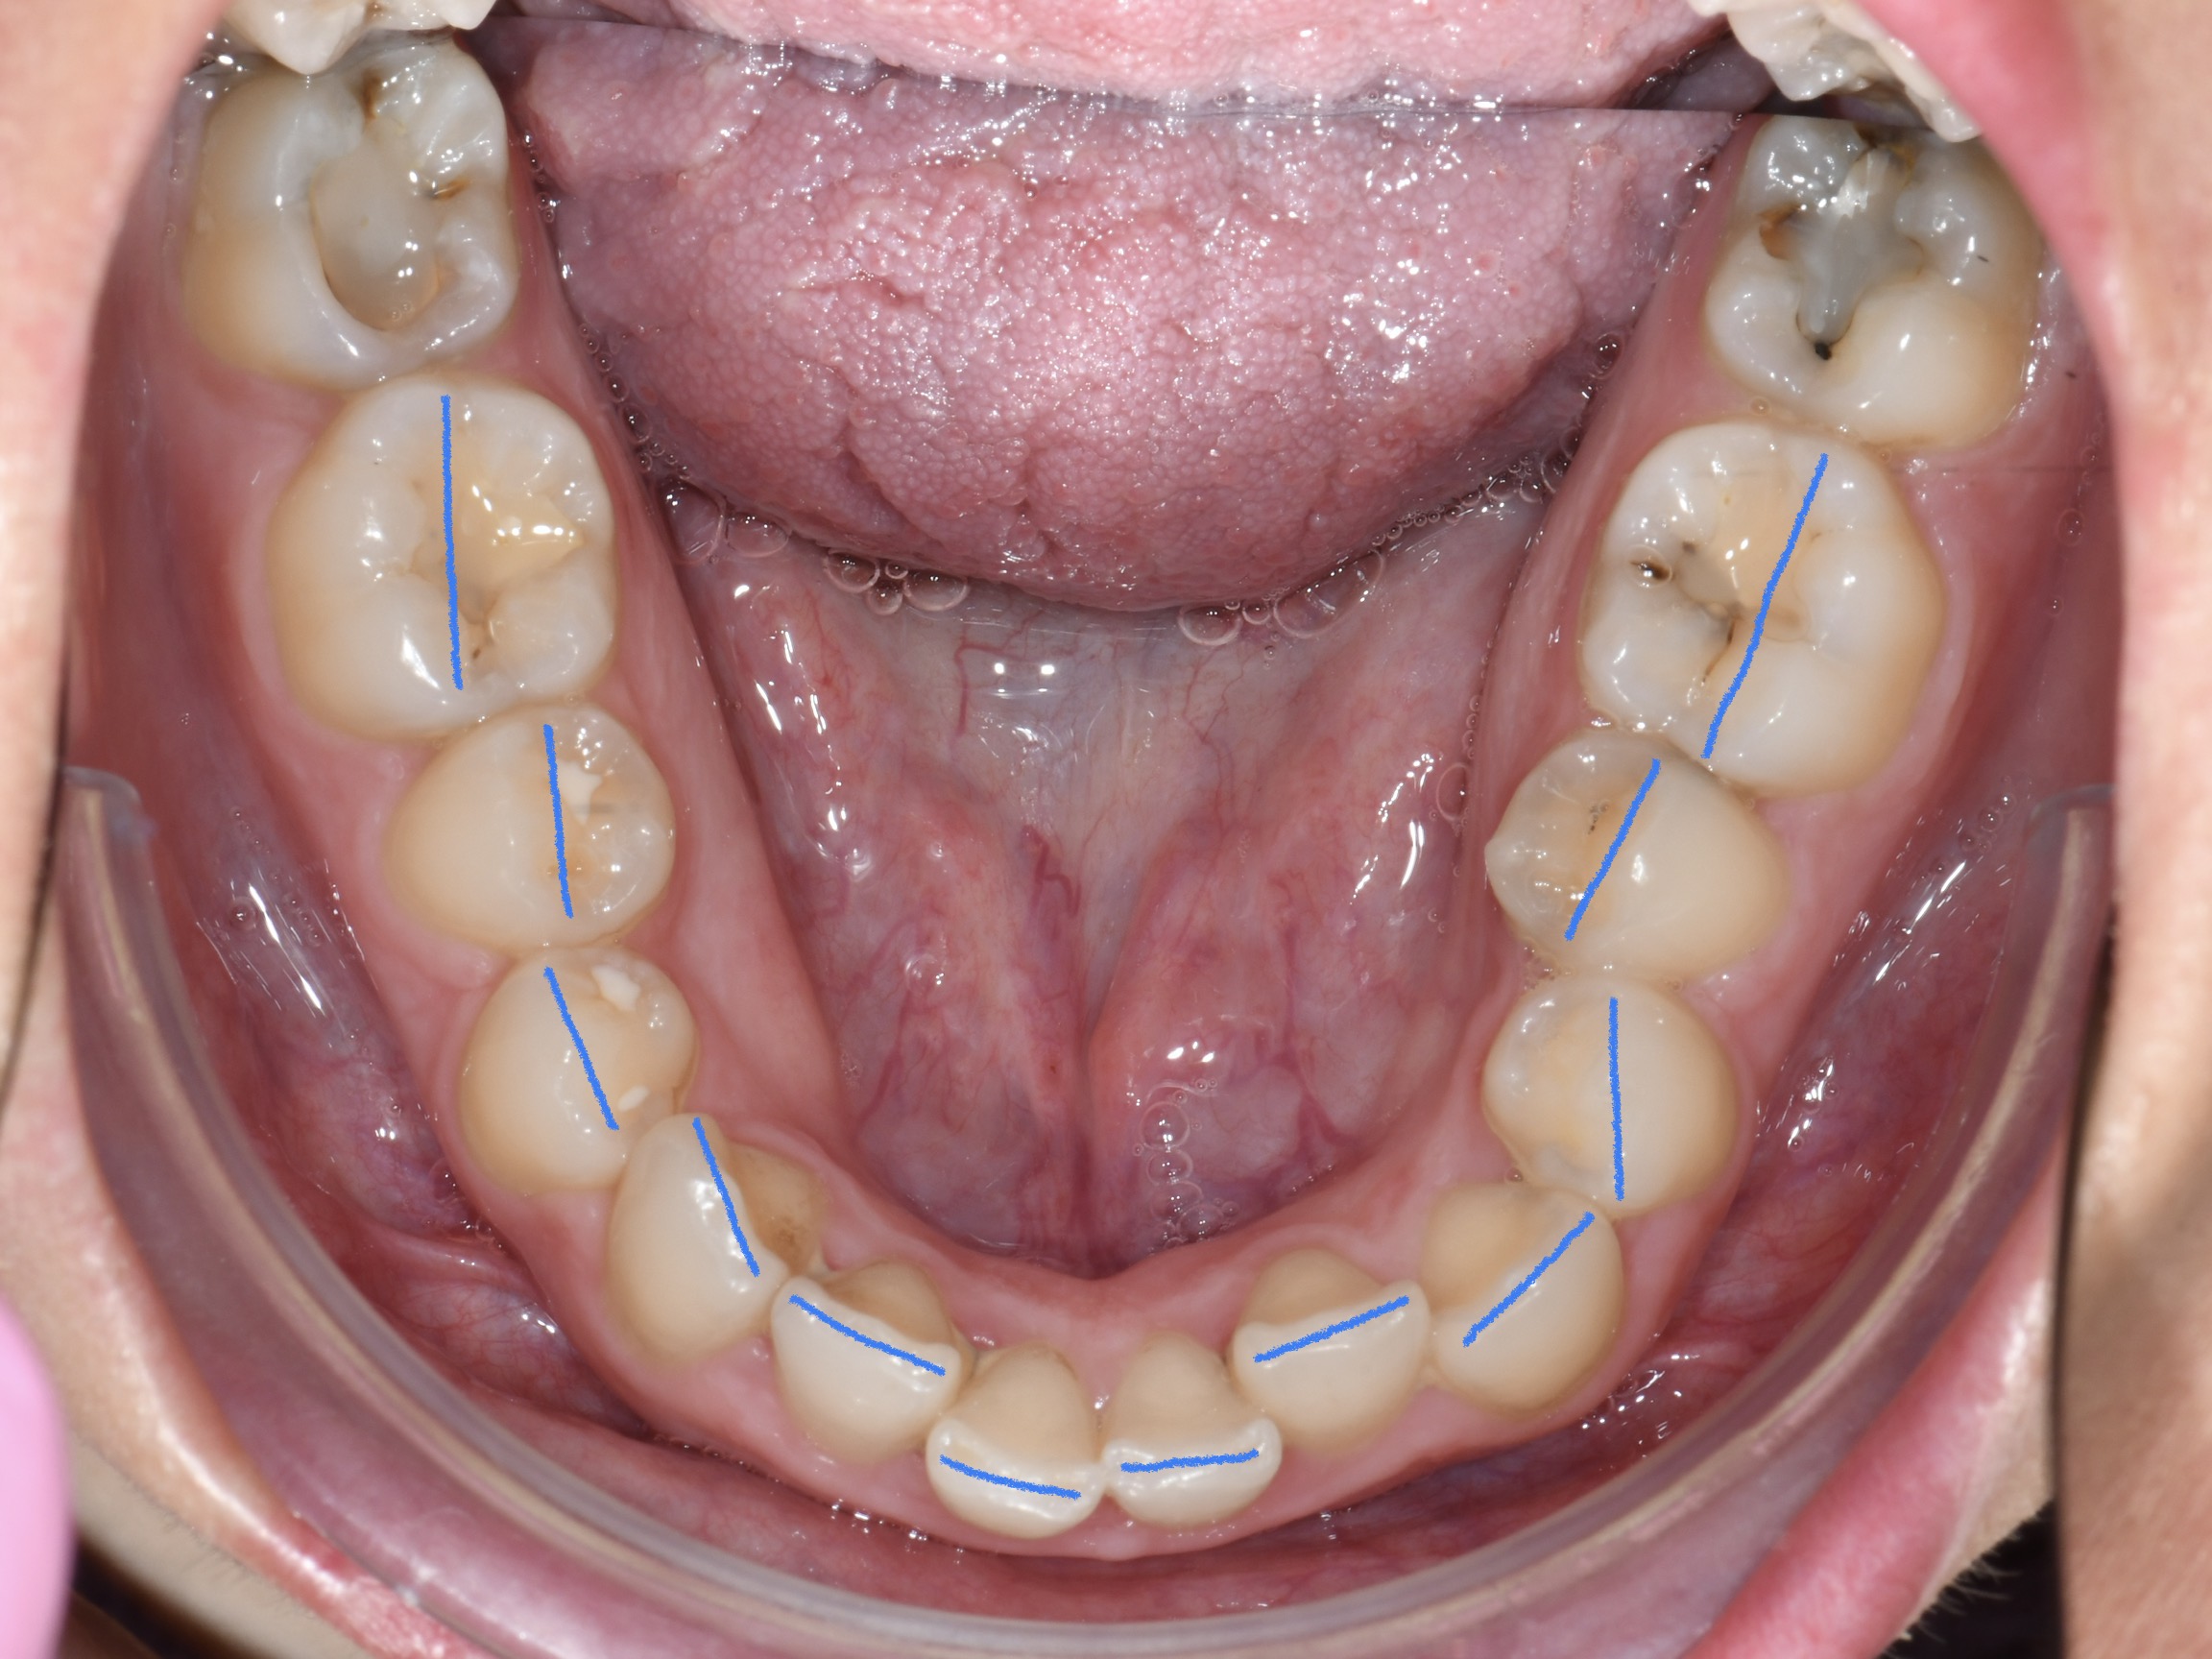

Az elmúlt évekből rengeteg szakmai referenciát tudnánk bemutatni, amelyek különböző fogszabályozási problémákat oldottak meg. Válogatva a több száz esetből, ezen az oldalon olyan képeket, információkat igyekeztünk bemutatni, amelyeknek a segítségével a jövőbeni pácienseinknek azt tudjuk üzenni: A Te fogsorod is lehet gyönyörű!

(Képeket a Pácienseink külön írásos beleegyezésével mutatjuk be!)